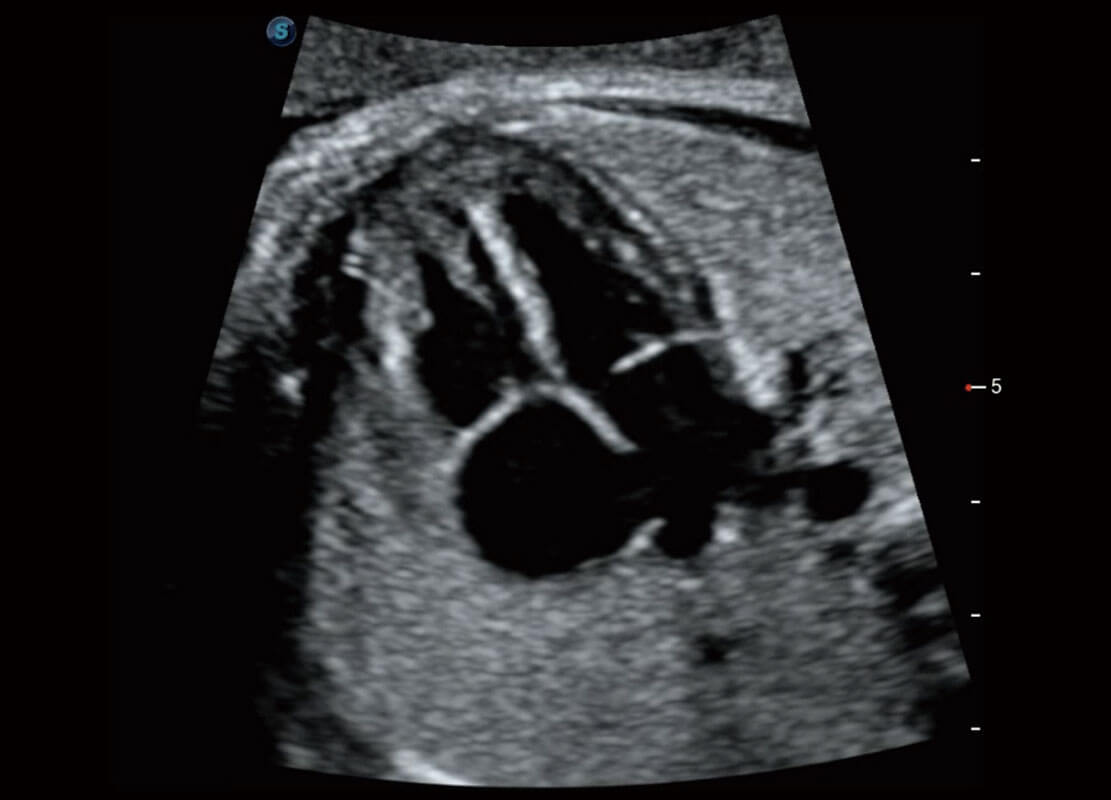

P60搭載一系列胎兒心臟成像技術(shù),實現(xiàn)精細的胎兒心臟評估。

四腔切面

四腔心血流